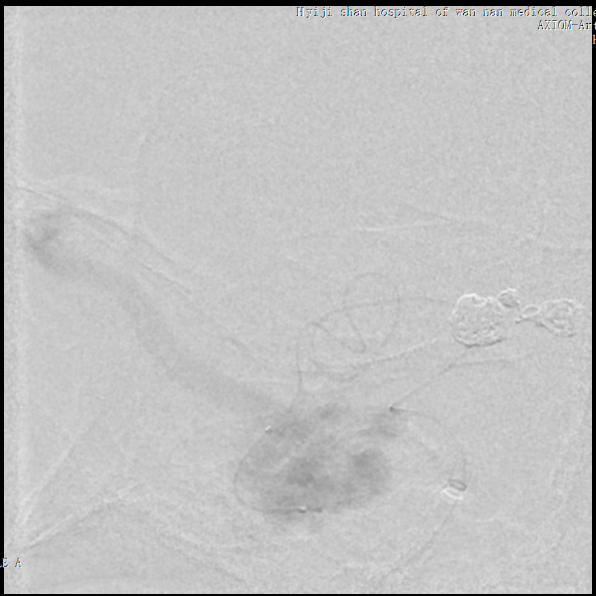

将Echelon 10微导管超选至右侧大脑中动脉分叉部分支血管远端,微导管造影确认系畸形团供血动脉,DMSO冲管后注射Onyx胶再行造影,可见该分支血管远端闭塞,予以撤出Echelon 10微导管。

用Apollo微导管超选大脑中动脉M1段分支血管直至畸形团内,进行微导管造影确认微导管进入畸形团,DMSO冲管,缓慢注射Onyx 18,路图下可见胶在畸形团内弥散,最后颈内动脉造影可见畸形团完全不显影,但是胶反流导致拔管困难,透视下可见血管移位变形明显。